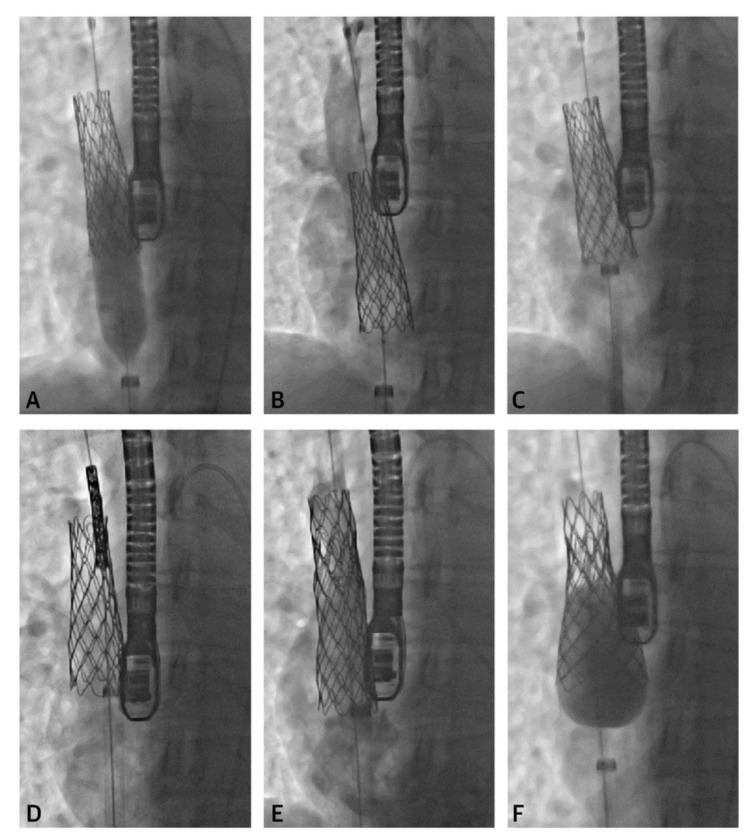

Management of congenital heart disease (CHD) has recently increased utilization of cross-sectional imaging to plan percutaneous interventions. Cardiac computed tomography (CT) and cardiac magnetic resonance (CMR) imaging have become indispensable tools for pre-procedural planning prior to intervention in the pediatric cardiac catheterization lab. In this article, we review several common indications for referral and the impact of cross-sectional imaging on procedural planning, success, and patient surveillance.

先天性心脏病(CHD)的管理最近增加了对横断面成像的利用,以规划经皮介入治疗。心脏计算机断层扫描(CT)和心脏磁共振(CMR)成像已成为小儿心导管实验室介入治疗前程序规划中不可或缺的工具。在本文中,我们回顾了转诊的几个常见指征以及横断面成像对程序规划、成功率和患者监测的影响。

Transcatheter Correction of Superior Sinus Venosus Atrial Septal Defects as an Alternative to Surgical Treatment.

J Am Coll Cardiol. 2020 Mar 24;75(11):1266-1278. doi: 10.1016/j.jacc.2019.12.070.